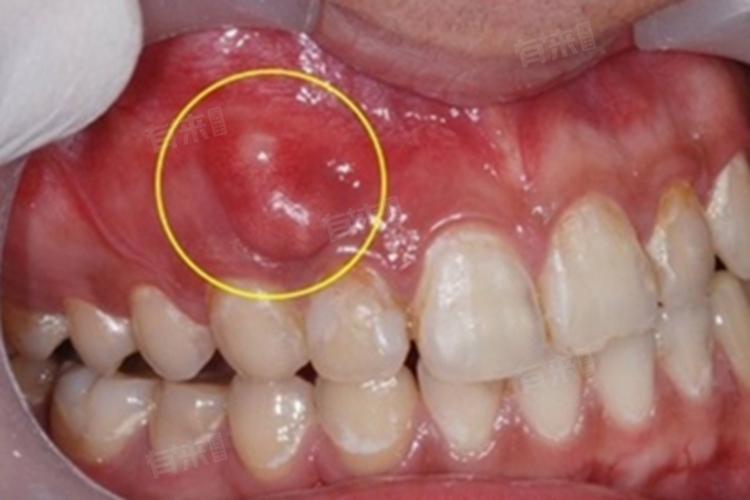

2、根尖周炎:通常是由于牙髓感染未得到及时治疗,炎症扩散到根尖周围组织引起的。细菌通过牙髓腔侵入根尖周,引起根尖周组织的炎症反应,导致牙根肿胀。患者会感到牙齿咬合疼痛,有时疼痛会放射到头部和面部。

牙根肿胀是一种常见的口腔问题,考虑与牙周炎、根尖周炎、龋齿、牙齿外伤,以及医源性因素等有关。如果出现牙根肿胀的情况,应及时就医,进行详细的口腔检查。